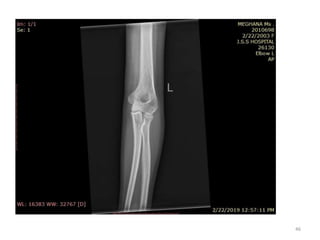

Elbow joint

• Secondary ossification Centres : (3 bones; 6 Ocs)

Capitulum (C) - appearance - 1 year of life

Head of Radius (R)– appearance -4 to 5 years

Medial Epicondyle (ME)

Appearance – 5 to 6 years

Fusion – 16 to 17 years

Trochlea (T) – appearance – 9 to 11 years

Olecranon Process of Ulna (OP)

Appearance - 8 to 9 years

Fusion- 16-17 years

Lateral Epicondyle(LE) – 11 to 12 years

Conjoint (Composite)Epiphysis (CE) [fusion of C+T+LE]

Formation – 14 to 16 years

Fusion – 16-17 years

Note: Fusion of O.Centres at elbow joint is 16-17 years in male, 15-16 years in female

Elbow joint • Secondaryossification Centres : (3 bones; 6 Ocs) Capitulum (C) - appearance - 1 year of life Head of Radius (R)– appearance -4 to 5 years Medial Epicondyle (ME) Appearance – 5 to 6 years Fusion – 16 to 17 years Trochlea (T) – appearance – 9 to 11 years Olecranon Process of Ulna (OP) Appearance - 8 to 9 years Fusion- 16-17 years Lateral Epicondyle(LE) – 11 to 12 years Conjoint (Composite)Epiphysis (CE) [fusion of C+T+LE] Formation – 14 to 16 years Fusion – 16-17 years Note: Fusion of O.Centres at elbow joint is 16-17 years in male, 15-16 years in female 35

ELBOW JOINT All OCsAppeared and fused (>16-17 years) 36